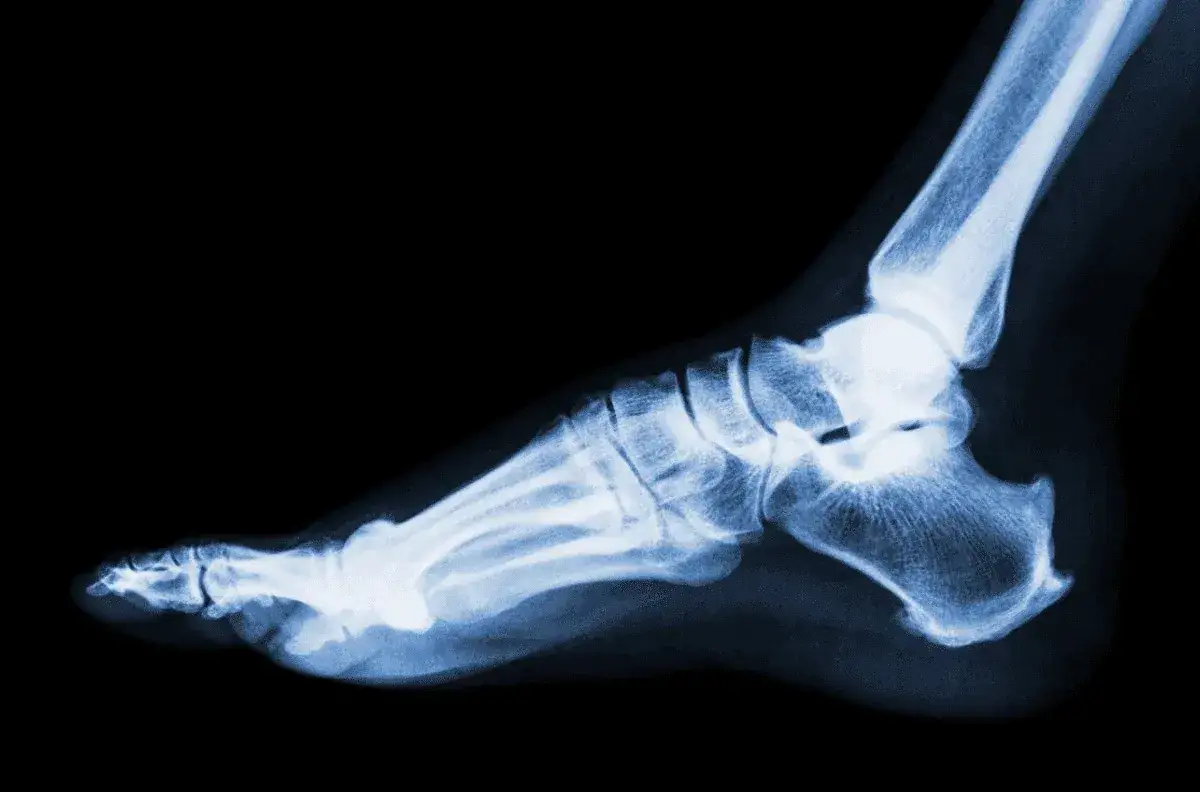

W artykule przyjrzymy się różnym rodzajom skręceń, ich objawom oraz czasowi rekonwalescencji. Zrozumienie, jak długo można spodziewać się bólu, jest kluczowe dla skutecznego zarządzania urazem oraz powrotu do pełnej sprawności. Pamiętajmy, że nawet po ustąpieniu objawów, warto skonsultować się z fizjoterapeutą, aby uniknąć nawrotów urazu.

Po skręceniu nogi, czas trwania bólu jest zróżnicowany i zależy od stopnia urazu. W przypadku skręcenia I stopnia, które jest najmniej poważne, ból zazwyczaj ustępuje w ciągu 7 do 10 dni. Osoby z tym urazem często doświadczają jedynie niewielkiego bólu i lekkiego obrzęku, co oznacza stosunkowo szybki powrót do zdrowia. Warto jednak pamiętać, że każdy organizm jest inny, więc czas gojenia może się różnić.

Dla skręcenia II stopnia, ból może utrzymywać się od 10 dni do kilku tygodni, a rehabilitacja w tym przypadku trwa przeciętnie od 4 do 6 tygodni. Skręcenie III stopnia, które jest najcięższe, może powodować ból przez kilka miesięcy, a pełna regeneracja może wymagać znacznie dłuższego czasu, czasem nawet interwencji chirurgicznej. Dlatego tak ważne jest, aby monitorować objawy i dostosować tempo powrotu do aktywności do własnych możliwości.